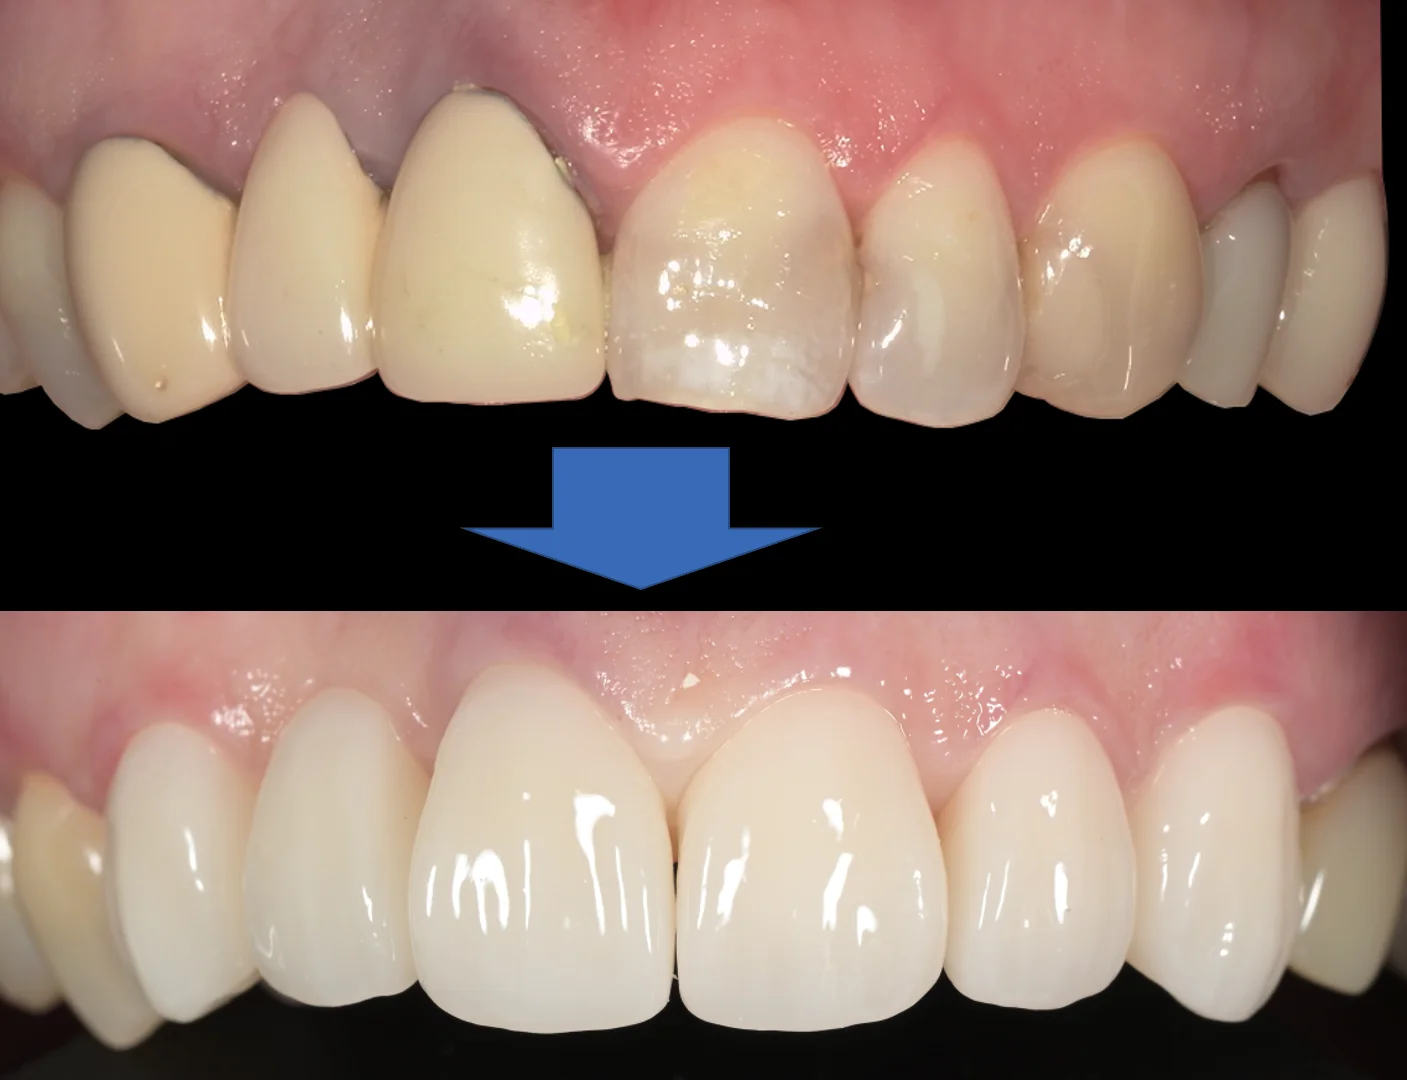

術前術後です。

撮影日が別日のため、画角がずれてしまっていますが、随分と見た目が綺麗になったのはわかると思います。